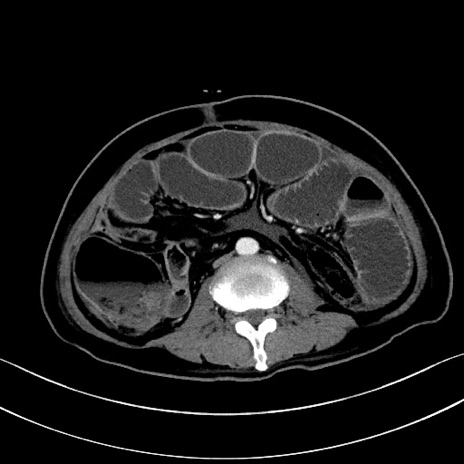

症例28(横断像)

【症例】60歳代男性

【主訴】嘔吐

【現病歴】胃癌にて胃全摘後。食思不振が悪化し、夜中に嘔吐することがある。

【既往歴】胃癌、胃全摘、脾摘、胆摘後

【データ】WBC 5900、CRP 10.56